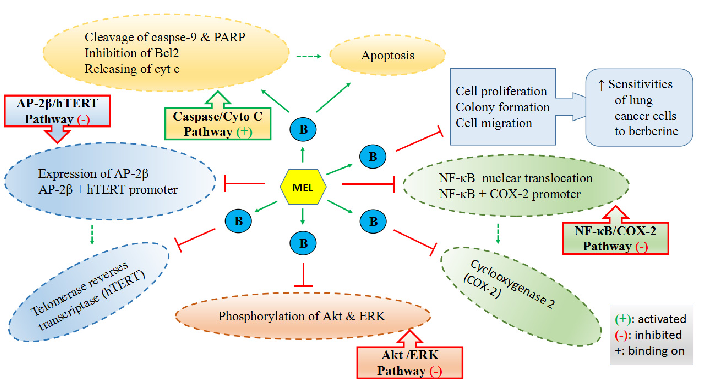

Mechanisms by which melatonin enhances lung cancer cell sensitivity to berberine are diagrammed, showing synergistic effects on apoptotic and autophagic pathways.

Dietary Sources and Bioactivities of Melatonin.